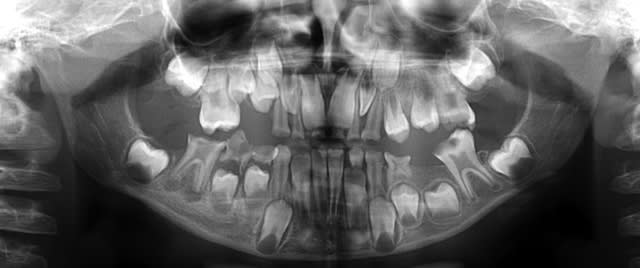

A 7 ans, cette demoiselle a eu une AG avec extractions de 14 dents temporaires.

A 10 ans, coca et chips à volonté, voici ses 11/21. Les 6 sont dans un état similaire.